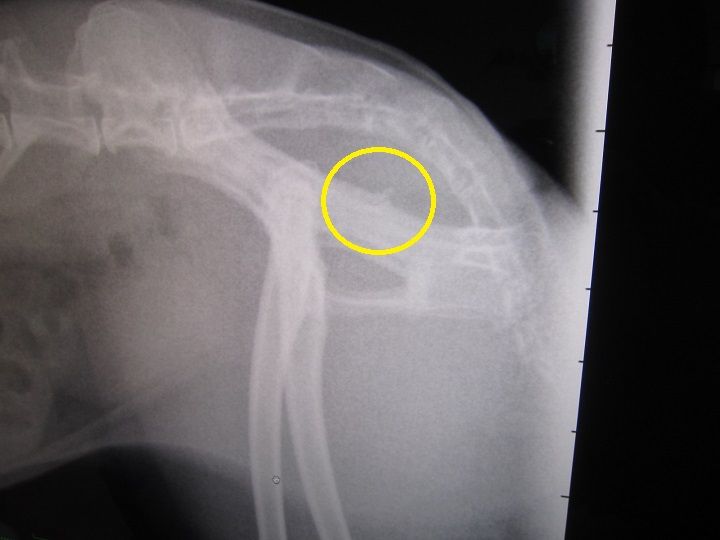

昨夜からの流れを話しし、診察、レントゲン

脂肪、すご過ぎやん…( ̄ェ ̄;)

前回との比較…

前回… とは、最初、あんまりにも食べない食べないで、きちんと痩せた状態、だったので余計かもですが、それでもマズい…

体重の数字や触った感じで気にはなってたから、

ずっとペレットは朝晩5gずつ。…だのに、増える体重、結果こんな…

他にもこんな子ざらにいます、でも、いるからOKて話ではなく、

体質やから仕方ない、って、片付けるには早すぎると思うし、

何より肥満って何かにつけてリスクの確率は通常より上がるしな。